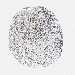

LIVER CANCER - Protein expressioni

A mouse-over function shows sample information and annotation data. Click on an image to view it in a full screen mode. Samples can be filtered based on level of antibody staining by selecting one or several of the following categories: high, medium, low and not detected. The assay and annotation is described here.

Note that samples used for immunohistochemistry by the Human Protein Atlas do not correspond to samples in the TCGA dataset.

Antibody stainingi

Antibody staining in the annotated cell types in the current human tissue is reported as not detected, low, medium, or high, based on conventional immunohistochemistry profiling in selected tissues. This score is based on the combination of the staining intensity and fraction of stained cells.

Each image is clickable and will lead to virtual microscopy that enables deeper exploration of all samples and also displays staining intensity scores, fraction scores and subcellular localization as well as patient and tissue information for each sample.

Antibody HPA008237

Antibody CAB017181

Staining

High

Medium

Low

Not detected

Intensity

Strong

Moderate

Weak

Negative

Quantity

>75%

75%-25%

<25%

None

Location

Nuclear

Cytoplasmic/membranous

Cytoplasmic/membranous,nuclear

Cholangiocarcinoma

Carcinoma, Hepatocellular, NOS